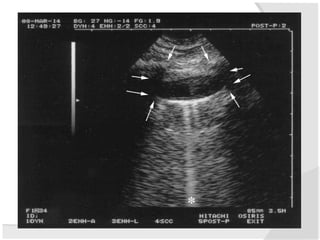

IVC Longitudinal

Landmarks

Aproach #2 – Anterior Mid-Axillary View

1 Place probe longitudinally in right anterior

mid-axillary line with marker towards the head

2 Look for IVC running longitudinally

adjacent to liver crossing the diaphragm.

3 Track superiorly until it enters right atrium

confirming that it is the IVC and not the aorta.

Measuring the IVC Diameter

Measure IVC 2cm

Inspiratory (Minimal) IVC

Diameter

Maximum (Expiratory) IVC

M-Mode IVC Diameters